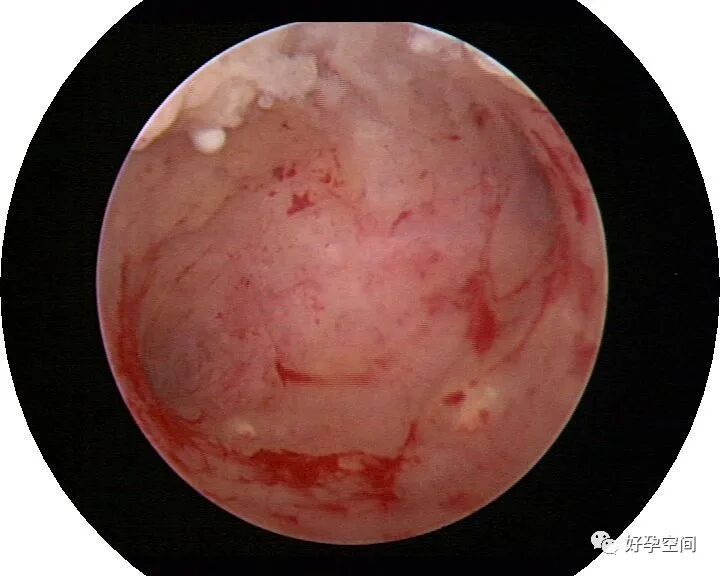

病例06:密布结节性肉芽肿内膜发红